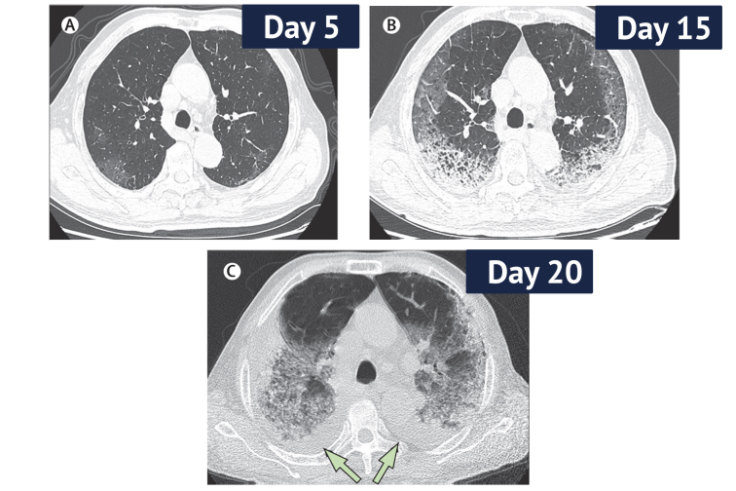

Ct Scans Of Coronavirus Patients Reveal Nature And Extent Of Lung Damage

Lung Scans Of Coronavirus Patients Show Damage Healing Over Time Business Insider

Radiological Findings From 81 Patients With Covid 19 Pneumonia In Wuhan China A Descriptive Study The Lancet Infectious Diseases

www.thelancet.com